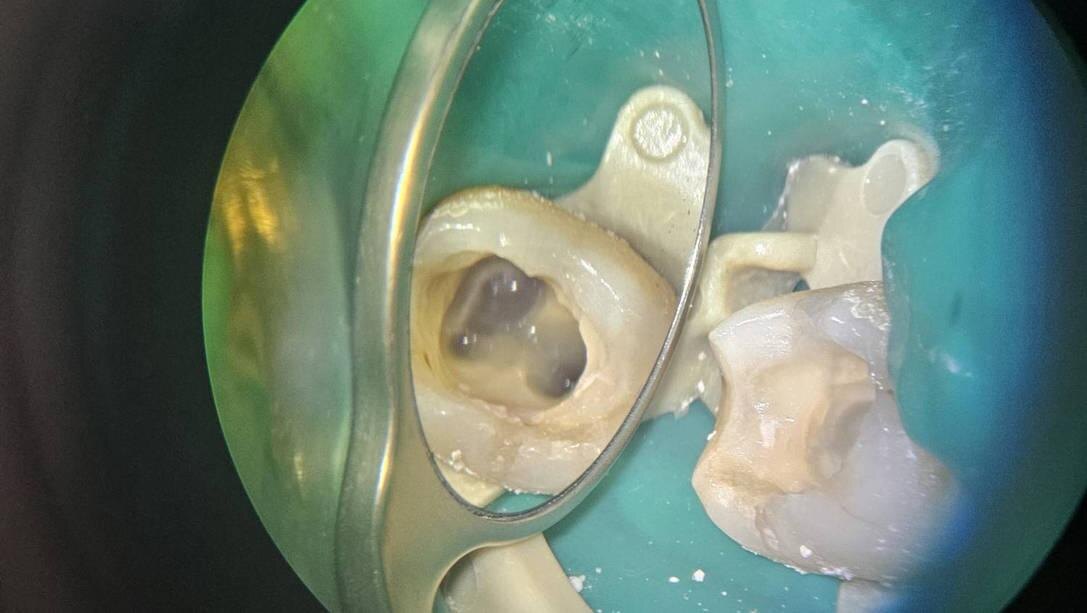

Зуб во время лечения под микроскопом

После купирования воспаления приступили к лечению. Под микроскопом быстро нашли канал, который и стал причиной страданий Вероники и неудачного предыдущего лечения.

Корневой канал, который стал причиной осложнения